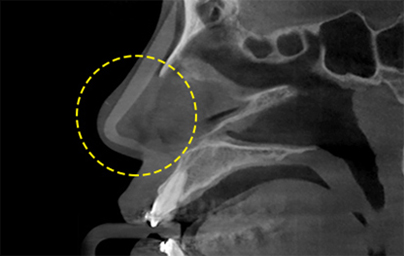

透過立體的骨骼圖進行精準診斷的 3D CT